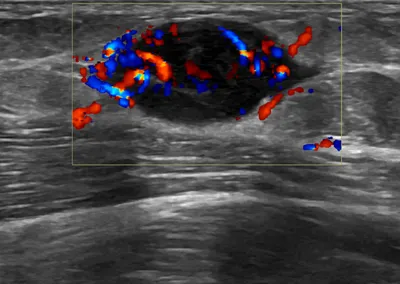

- This collection contains 4 radiology images related to forearm, including various imaging modalities such as X-rays, MRIs, CT scans, and ultrasound images commonly used in medical diagnosis and education.